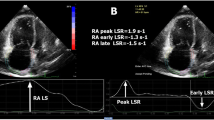

In each patient, 2-dimensional strain analysis was performed offline by use of a dedicated software package (EchoPAC, version BT13) which evaluates real-time tracking of natural acoustic markers during two consecutive 2-dimensional grayscale images taken at a frame rate of 60–80 frames/s. For assessment of RV peak longitudinal systolic strain, images taken at a frame rate of 60–80 frames/s were obtained from the apical 4-chamber view. Three consecutive cardiac cycles were acquired and digitally stored for offline analysis. The RV endocardial border was manually traced in the end-systolic frame. The region of interest (ROI) in each image was automatically generated. The position of the ROI and its width were adjusted manually when the speckle tracking appeared to be poor. The software then automatically tracked and accepted segments of good tracking quality and rejected poorly tracked segments. When all segments of RV were accepted, the regional longitudinal strain curves were obtained for six segments of RV. After that, segmental values of peak longitudinal systolic strain from the basal, mid, and apical segments of the RV free wall were recorded. Representative examples of regional longitudinal strain curves taken from the right ventricle by STE were shown in Figs. 1 and 2.

RV regional longitudinal function

PLSS values from the basal, mid, and apical segments of the right ventricular lateral wall are listed in Table 3. PLSS values from the apical segment of the RV free wall were significantly lower in the PAH group compared with the non-PH group at baseline (− 14.6 ± 5.9 vs. − 22.2 ± 7.5, p = 0.034). At the same visit, PLSS values from the basal and mid segments of the RV free wall were also lower in the PAH group, but these differences between the two groups were not statistically significant. PLSS at the basal, mid, and apical segments of the RV free wall were lower in both groups at follow-up compared to baseline, but the reduction of strain values was statistically significant only in the non-PH group (p < 0.05 for all).